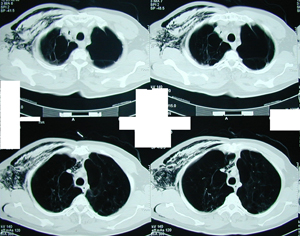

Εικόνα 3 α-ε

Αξονική τομογραφία του θώρακος. Διακρίνεται η παρουσία μεγάλου πνευμοθώρακος παρά την ύπαρξη της παροχέτευσης και την σύνδεση της συσκευής Bullau με συνεχή αρνητική πίεση. Επίσης υπάρχουν πολλαπλές μεγάλες εμφυσηματικές φυσαλίδες αμφοτερόπλευρα. Επιπλέον υπάρχει εκτεταμένο υποδόριο εμφύσημα.

Α-Β

Γ-Δ